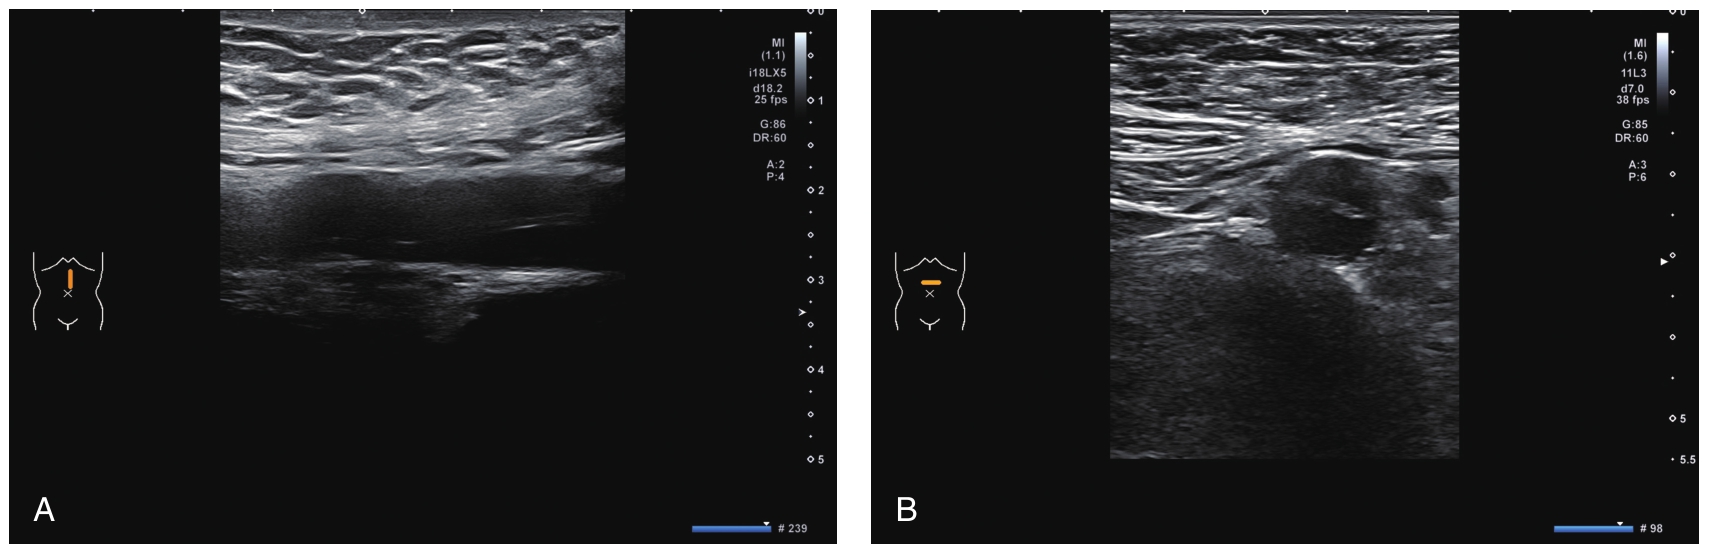

二维灰阶超声:腹主动脉下段内见漂浮线状高回声,将腹主动脉分为真假两腔(图9-1A、B),真腔内径约6mm,假腔内径约5mm。夹层累及长度约3.0cm。上方破口距肾动脉约3.0cm,下方破口近腹主动脉骑跨处,未累及髂动脉。肾动脉、肠系膜上动脉、肠系膜下动脉开口于正常腹主动脉,血流通畅。

图9-1 腹主动脉夹层动脉瘤超声图像

二维灰阶超声(A、B)示腹主动脉下段见漂浮线状高回声。CDFI(C)示真腔、假腔血流均充盈良好。脉冲多普勒超声(D、E)示真腔、假腔血流流速基本一致。